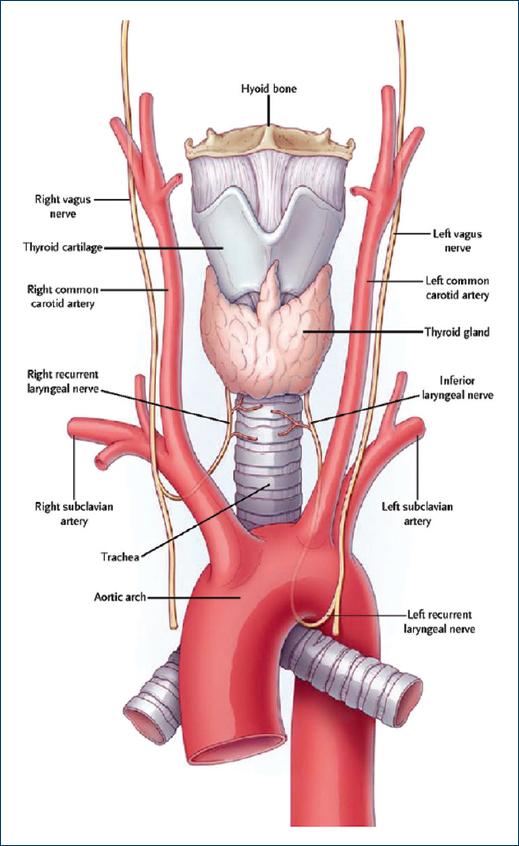

Although rare, RLN palsy has been documented in 1.3% of cases of classical SCB13. It has mostly been reported in the right-sided block which is well explained by its relationship with the right subclavian artery (SCA). The right and left RLNs follow different courses14 (Fig. 1). The right RLN encircles the right SCA and is in its close proximity. Hence, there are chances of its involvement in rare cases when a large amount of LA is deposited near the artery where the RLN is located. Hence, when the drug is deposited near SCA, there remains the possibility of involvement of RLN due to close proximity of the neurovascular structure, and more so when a large volume of the drug has been deposited15. However, the left RLN is much medial in relation to the left SCA running closer to trachea and esophagus. It is the left vagus nerve which runs near the SCA. The mechanism by which the nerve block occurred in our case was the exclusive block of the fibers of RLN present in the vagus nerve or unilateral vagus nerve as the drug deposited moved medial to the SCA and since the RLN is located farther. Visualization of the tip of the needle throughout the procedure is of utmost importance as this prevents the puncture of unwanted structures preventing complications and increases the chances of success of the procedure by deposition of LA at exact location16-18 (Fig. 2). The fascial sheath surrounding the brachial plexus is a determinant for the spread of LA. The sheath is a derivative of the deep cervical fascia and terminates by merging with the medial intermuscular septum of the arm. The LA injected spreads up and down the nerves in a longitudinal manner and circumferential spread are limited by the fascial sheath. When the large volume of LA is injected, there is a possibility of proximal spread of excessive drug involving RLN and attributing the hoarseness of voice19. As it happened with our patient the volume of the drug used might have been an additional contributing factor for the excessive spread. There is a remote possibility of aberrant left RLN (incident 0.04%) when it is known as non-recurrent inferior laryngeal nerve, it runs closer to the SCA and is always associated with aberrant vessels such as arteria lusoria, right aortic arch, and situs inversus20. Cases have been reported of respiratory obstruction as a result of unilateral SCB plexus block. In our case, it was self-limited; it only caused a feeling of discomfort in the patient. For similar reason, interscalene brachial plexus block should be avoided21,22. Various techniques have been described to limit the spread of injected LA into the brachial plexus23. These include the use of tourniquet position of the arm, use of massage of the area for around 5-10 min, multiple injection techniques, digital pressure proven by Gupta et al.8, and elevated the head end of the bed by 30°. Based on the radiological evidence, digital pressure has been touted as an effective method to halt progression of LA into areas of the brachial or cervical plexus during brachial plexus block24.

Figure 1 Anatomical relationship of recurrent laryngeal nerve right and left. Downloaded from nejm.org.